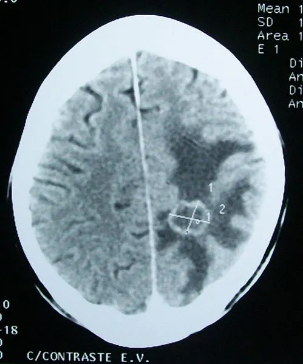

通过CT确认的脑部肿瘤。图片来源:wikipedia